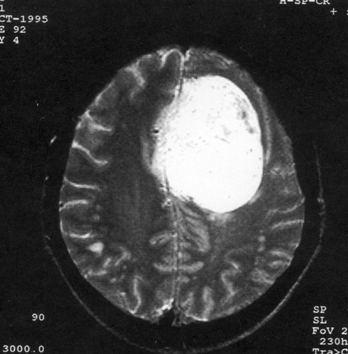

问题 病历摘要:??患者女性,37岁。大便时突起炸裂样头痛3小时,伴喷射样呕吐。既往体健。体检:T37.5℃,BP145/90mmHg,R20次/分,P85次/分。神志清楚,颅神经检查无异常,颈强直,克、布氏征(-),四肢肌力、肌张力正常,病理征(-)。 按Hunt&?Hess的动脉瘤危险性分级,该患者可分为几级?